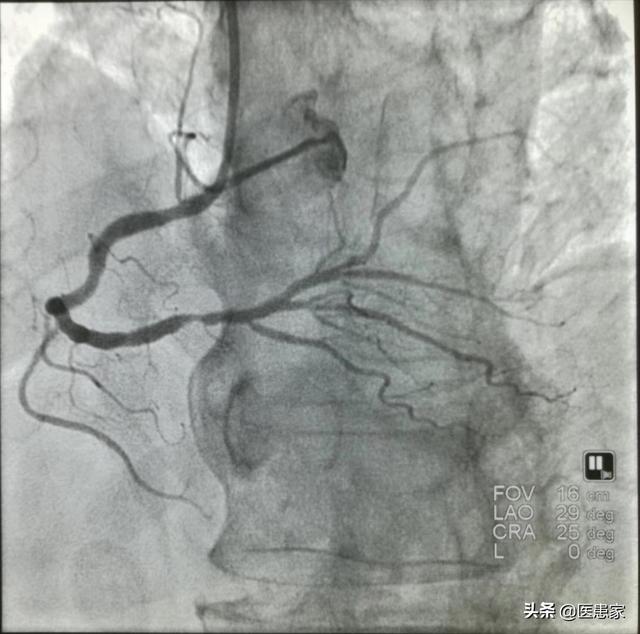

Dans des circonstances normales, les artères coronaires sont au nombre de deux, à savoir les couronnes gauche et droite, et la couronne gauche peut être divisée en deux branches, à savoir la branche descendante antérieure et la branche échogène ; la couronne droite envoie des branches principales telles que la branche conique artérielle, la branche marginale droite, la branche du nœud sinusal, la branche du nœud auriculo-ventriculaire et la branche interventriculaire postéroventriculaire ; et la branche descendante antérieure envoie les branches principales telles que la branche conique artérielle, la branche postéro-médiane et la branche septale interventriculaire. Toutes ces artères coronaires assurent l'irrigation sanguine du cœur, en alimentant une certaine zone du cœur, garantissant ainsi que les cellules de travail et les cellules autorégulatrices du cœur sont correctement alimentées, ce qui permet au cœur de battre à un rythme et à une fréquence normaux.

La sténose coronarienne peut être classée en quatre catégories : une sténose de 25 à 49 % est appelée sténose de grade 1, une sténose de 50 à 74 % est appelée sténose de grade 2, une sténose de 75 à 99 % est appelée sténose de grade 3 et une sténose de grade 4 est appelée sténose de 100 %, c'est-à-dire une occlusion complète du vaisseau sanguin, ce qui correspond à ce que nous appelons une crise cardiaque.

Sténose coronaire de plus de 70 % pour une sténose secondaire, c'est-à-dire une sténose modérée, théoriquement parlant, n'a pas encore atteint le troisième degré de sténose, il n'est pas nécessaire d'implanter un stent coronaire ; mais il y a une chose à laquelle nous devons faire attention, le danger de la sténose coronaire dépend principalement de l'emplacement de la lésion, par exemple, le tronc principal gauche de la lésion est très dangereux, le médecin l'appelle souvent la "branche de la veuve", parce que la plupart de l'approvisionnement en sang du ventricule gauche provient du tronc principal gauche. Par exemple, le blocage de l'artère coronaire au niveau du nœud sinusal ou du nœud auriculo-ventriculaire provoquera une arythmie grave, voire mortelle. S'il s'agit d'un blocage des vaisseaux sanguins périphériques, les dommages seront relativement moindres.

En principe, le traitement de la maladie coronarienne devrait privilégier le traitement conservateur, c'est-à-dire le traitement par médicaments oraux, l'amélioration du mode de vie, etc., et le traitement traumatique tel que l'implantation d'une endoprothèse coronaire ou un pontage aorto-coronarien ne sera choisi qu'en cas d'inefficacité du traitement conservateur.

En résumé, la gravité d'une sténose coronaire de plus de 70 % dépend de la localisation de la lésion, et il est recommandé aux patients de consulter un professionnel de la santé pour choisir la meilleure option de traitement s'ils ont besoin d'implanter un stent.